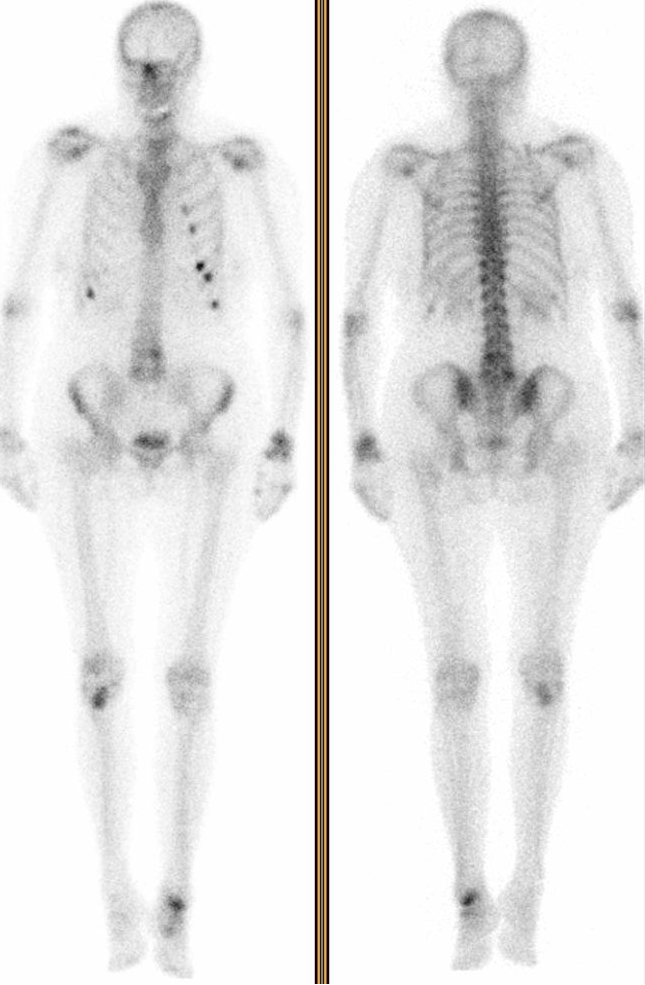

Scintigraphie osseuse réalisée dans le bilan de douleurs costales post traumatiques chez une patiente de 65 ans.

Le foyer de fixation tibial supérieur droit est exploré en SPECT CT

Substitut osseux non osseux à base de sulfate de Calcium permettant une régénération osseuse.

substitut de synthèse osseux sur lésion bénigne du plateau tibial

Il s’agit vraisemblablement d’une lésion osseuse non traumatique opérée il y a longtemps (a priori bénigne…).

L’activité ostéoblastique reste importante à distance de l’intervention.

Il s’agit effectivement d’un substitut osseux utilisé pour combler une lésion bénigne kystique fragilisante. c’est un substitut d’origine non osseuse, vraisemblablement du plâtre de Paris (Ostéoset) à base de sulfate de Calcium.